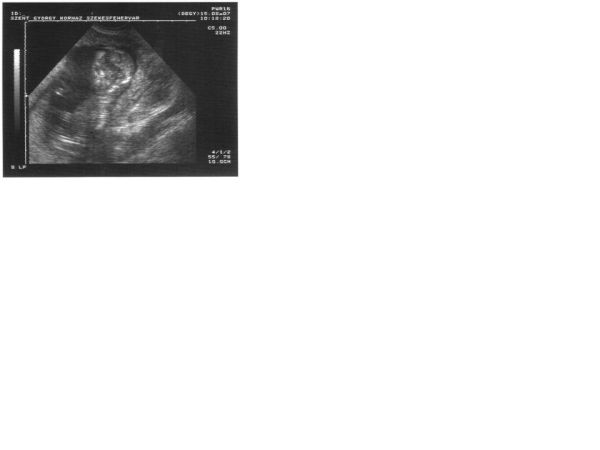

Lehet kislányod lesz tényleg!!!!